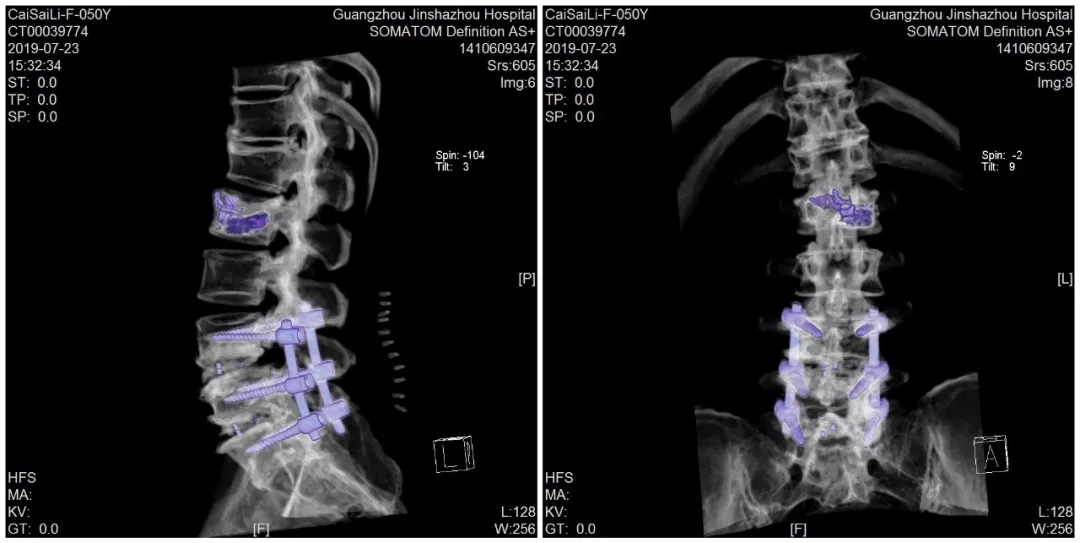

术后CT三维重建

于是经朋友介绍,蔡阿姨来到了我们金沙洲医院骨科中心求诊。经检查提示腰2椎体压缩性骨折,腰椎峡部裂。由于蔡阿姨的骨折和腰椎突出情况比较复杂,经过对蔡阿姨病情的详细评估,骨科中心分二次给蔡阿姨进行了手术。在我们见到蔡阿姨的时候,她第二次手术已经结束,除了下肢尚有一点点麻痹,医生说她其他方面恢复得很好,她看起来精神也不错。